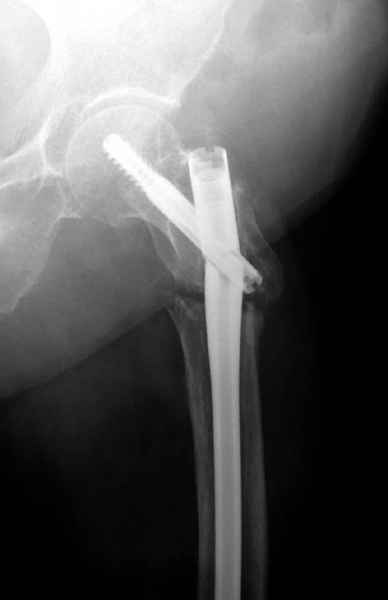

77 летняя больная направлена в нашу клинику на дальнейшее лечение. Из истории, травму получила в сентябре 2007 года и по поводу перелома шейки бедра больная была проперирована тремя каннюлированными шурупами с явным нарушением технологии установки шурупов. Внизу вместо одного шурупа имеется два, что привело к стрессу латерального кортекса. Через месяц по поводу ятрогенного подвертельного перелома сделана фиксация длинной Гамма 3. Установлен без проксимальной блокировки? (set screw). В данный момент имеется несостоятельность конструкции и ложный сустав. Передвигается с помошью костылей, конечность укорочена на 2 см. Какие будут рекомендации?Djoldas Kuldjanov, MDDepartment of Orthopedic SurgerySt. Louis University Medical Center

Видимо, проблем тут две: во-1-х, центральный отломок был оставлен в варусно-сгибательной установке, во-2-х, не динамизировали вовремя.

Нижние винты хотели сломаться, но, увы, один не сломался, и тогда сломался гвоздь. Хотя и при динамизации в таком положении отломков

могло не срастись.

Не стали усложнять интрамедуллярным вариантом коррекции, легче контролировать коррекцию пластиной, поэтому сделали операцию 95 градусной Blade Plate, разогнув до 110 градусов.

Надеемся на успех, потому что до введения пластины дефект от импланта забили костной стружкой и удалось создать компрессию между отломками, максимальную для импланта (150 кило/паунд). Сделана дополнительная костная пластика и за счет измененного угла пластины устранено укорочение конечности.